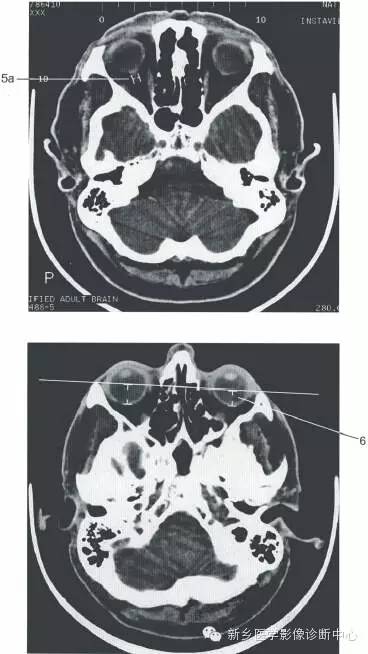

颅脑大体及磁共振断层解剖